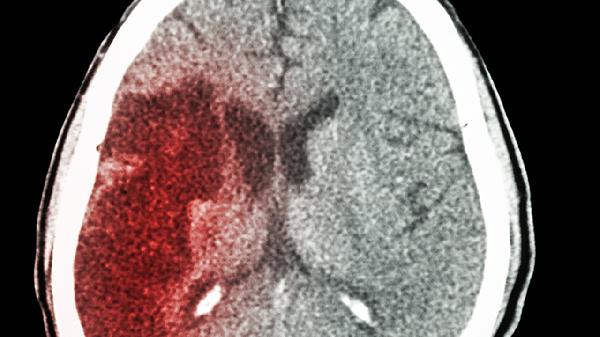

腿麻不一定是脑出血,可能是腰椎间盘突出、糖尿病周围神经病变、下肢血管病变、短暂性脑缺血发作或电解质紊乱等原因引起。脑出血引起的腿麻通常伴随剧烈头痛、呕吐、意识障碍等典型症状。

出现持续腿麻症状建议及时就医排查病因,日常注意保持规律作息,避免长时间保持同一姿势。控制高血压、糖尿病等基础疾病,适度进行快走、游泳等有氧运动促进血液循环。饮食上增加全谷物、深色蔬菜摄入,补充B族维生素。若突发腿麻伴随言语不清、面部歪斜等表现,需立即拨打急救电话排除脑血管意外。